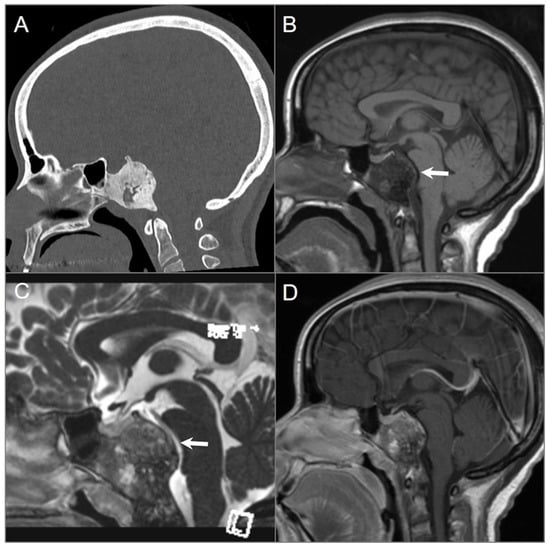

4.4.1. Chordoma

4.4.2. Chondrosarcoma

5.10. Ecchordosis Physaliphora